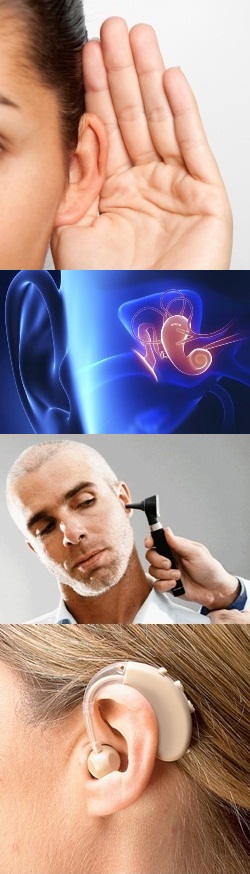

Современные слуховые аппараты при сенсоневральной тугоухости

Раздел: Лаборатория идей